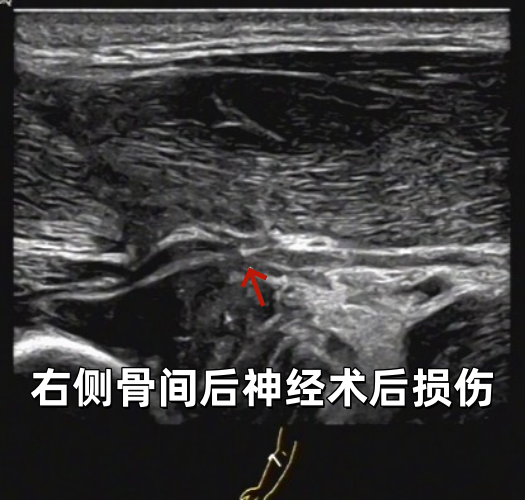

部分病例展示